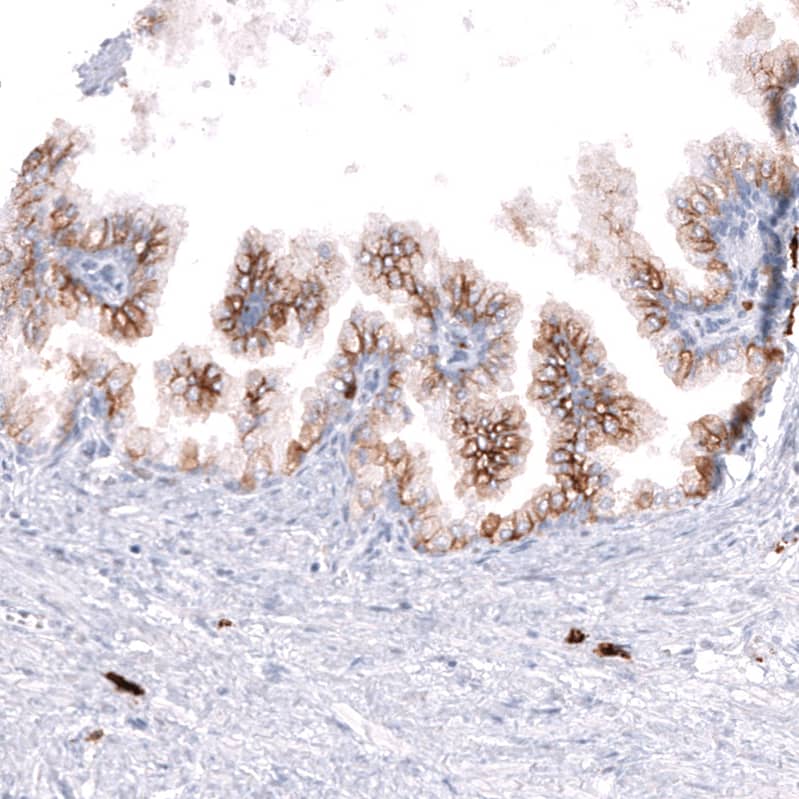

Staining of human prostate shows strong membranous positivity in glandular cells.